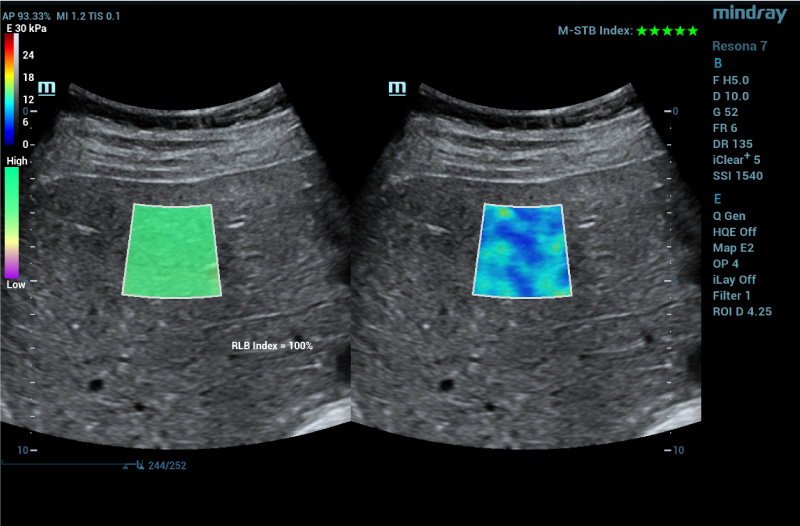

To address the changing needs of today’s value-based care environment, the Resona 7 Ultrasound System Platinum Edition was developed to capture clear, uniform images for radiology, vascular, women’s health, pediatric, and shared service imaging applications.

Premium imaging coupled with advanced workflow technologies help ease clinicians’ increasing workload by offering intuitive and easy-to-use smart tools and AI-enhanced technologies to elevate clinician and patient satisfaction. The user-directed ergonomic design is ideal for daily use, enabling clinicians to capture premium images without sacrificing comfort.